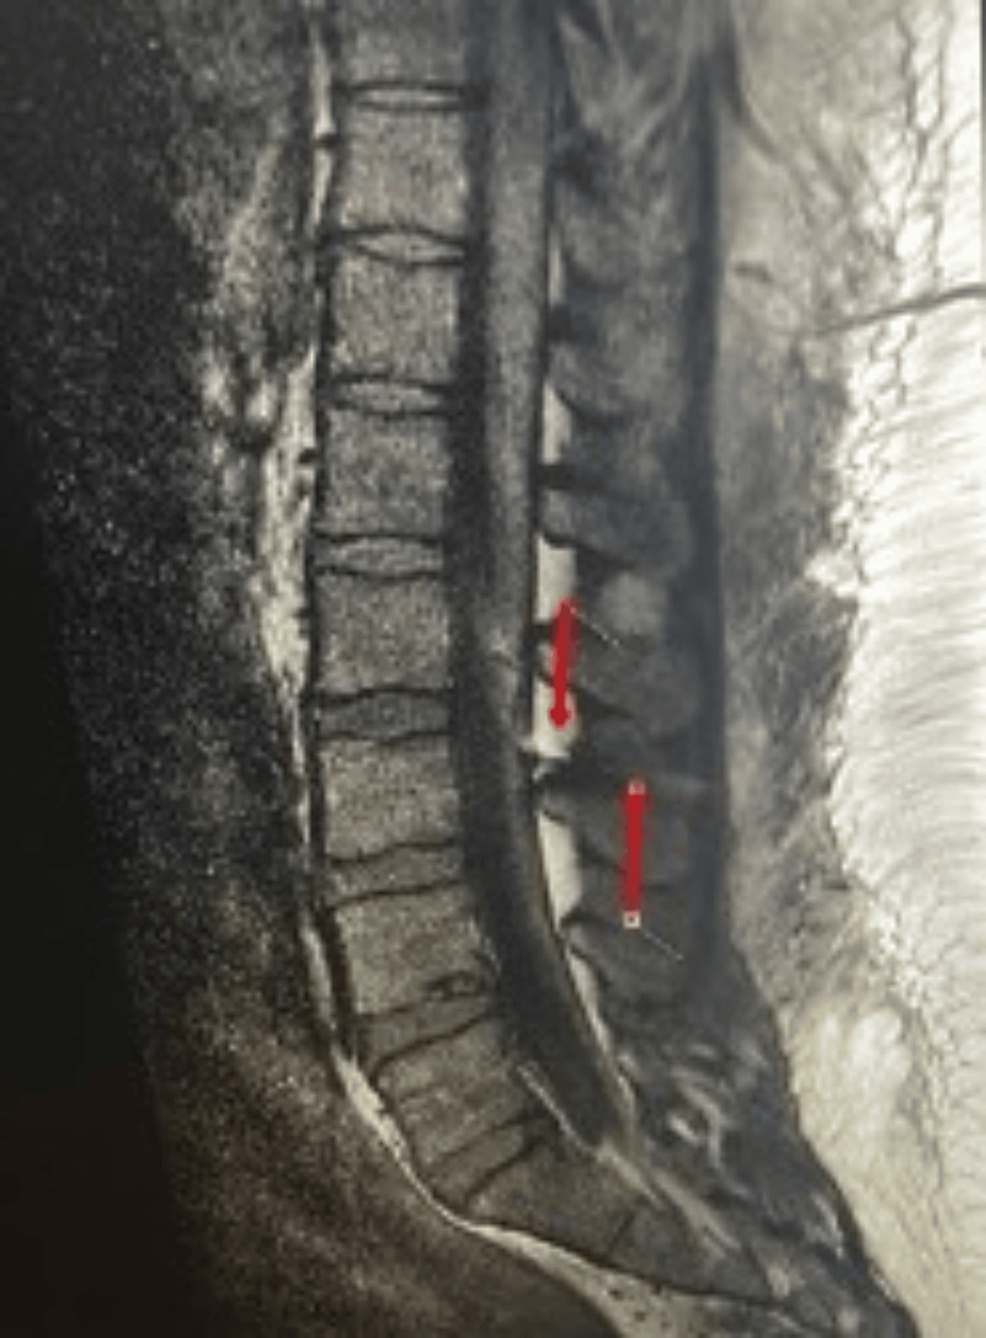

Computed tomography scan and resonance imaging showing Epidural Catheter Broke Off In Back Visualization of retained catheter is difficult. Catheter breakage is a recognised complication of epidural anaesthesia, often attributed to trauma on insertion or excessive. The epidural catheter was localized in the right paraspinal gutter and pulled out by using a blunt nerve hook. Hence, the decision was taken to remove the catheter, but as the catheter was being pulled off along. Epidural Catheter Broke Off In Back.